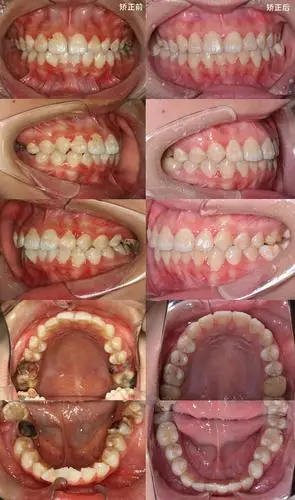

牙齿矫正效果惊人,矫正期间需要注意这几点,否则效果会大打折扣

相关图片

牙齿矫正的基本流程